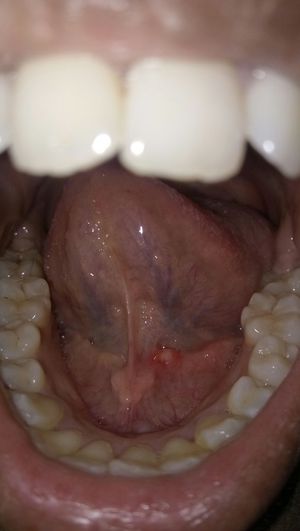

Diagnosis please

Diagnosis

Dx

Please

I'm thinking some sort of calculus formation in the ducts?

Acidity